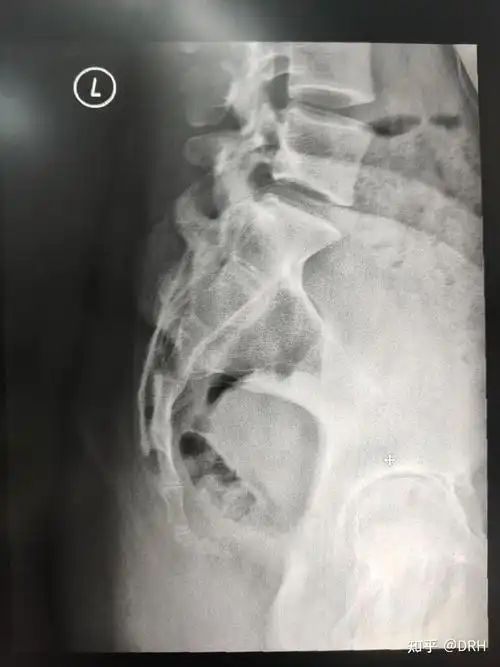

尾骨骨折是一种怎样的体验

骶尾椎影像报告怎么写? - 知乎

摔了一跤怀疑尾骨骨折或骨裂,去拍了片子遇到个庸医

x线,ct如何辨别骶尾骨骨折?看这篇就够了!-medsci.cn

如果不是孩子片子上提示尾骨断裂谁也想不到父亲的这脚有多重